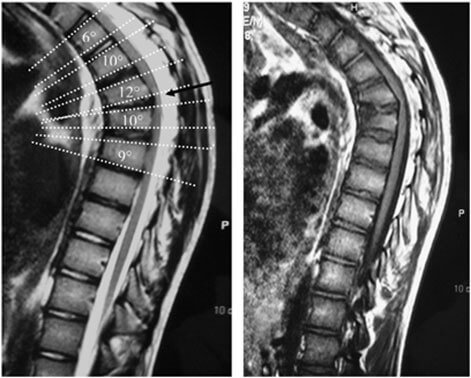

يُعاني بعض الأشخاص من آلام شديدة في منتصف وأسفل الظهر تمتد أحيانًا إلى البطن أو الفخذين، ويكتشف الأطباء بعد الفحص أن السبب هو انزلاق غضروفي في المنطقة الفاصلة بين منتصف وأسفل العمود الفقري، أي بين الفقرات T10 إلى L2. هذا النوع يُسمى الانزلاق الغضروفي الصدري القطني، ويُعتبر من الحالات النادرة مقارنةً بانزلاق الفقرات السفلية.

لكن المثير للاهتمام أن معظم المرضى الذين يعانون من هذا النوع من الانزلاق الغضروفي لديهم علامات مميزة في الأشعة تُشير إلى مرض شويرمان، وهو أحد اضطرابات نمو الفقرات خلال مرحلة المراهقة.

أثبتت دراسات حديثة أن هناك ارتباطًا وثيقًا بين انزلاق الغضروف في المنطقة الصدرية القطنية ووجود علامات لمرض شويرمان.

في إحدى الدراسات التي شملت 63 مريضًا أُجريت لهم جراحة للانزلاق الغضروفي الصدري القطني، وُجد أن أكثر من 95% منهم لديهم علامات تدل على وجود مرض شويرمان في الأشعة.

بمعنى آخر، معظم المصابين بالانزلاق في هذه المنطقة كانوا في الأصل يعانون من تشوه بسيط في شكل الفقرات نتيجة شويرمان، حتى لو لم يتم تشخيصهم من قبل.

السبب في ذلك أن الفقرات المتأثرة بمرض شويرمان تكون غير منتظمة الشكل أو مائلة قليلًا للأمام، مما يجعل الغضروف بين هذه الفقرات أكثر عرضة للضغط والتمزق، وبالتالي يحدث الانزلاق بسهولة أكبر.

يعتمد التشخيص على الأشعة المقطعية أو الرنين المغناطيسي لتحديد موقع الانزلاق وشكله، إضافة إلى ملاحظة وجود علامات شويرمان مثل:

عدم انتظام شكل الفقرات.

وجود نتوءات صغيرة داخل الفقرة.

ميلان الفقرات إلى الأمام أكثر من الطبيعي.

إذا تم العثور على هذه العلامات، يُرجَّح أن الانزلاق مرتبط بمرض شويرمان.